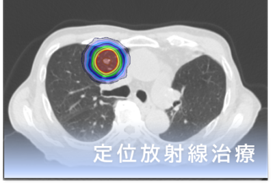

さらに当院では、体表面の形状を用いて位置や体動を確認するシステム(IDENTIFY) も導入しています。画像による確認に加えて体表面での確認も組み合わせることで、治療の安全性と再現性の向上に努めています。定位放射線治療(SRT・SBRT)や強度変調放射線治療(IMRT)など、病変や目的に応じた高精度治療にも対応しています。

近年の放射線治療の進歩は目覚ましく、「高精度放射線治療」といわれる、がん病巣へ正確に放射線治療を行いながら、かつ、がんの周囲にある正常組織にはあまり放射線を当てないよう工夫した治療ができるようになりました。